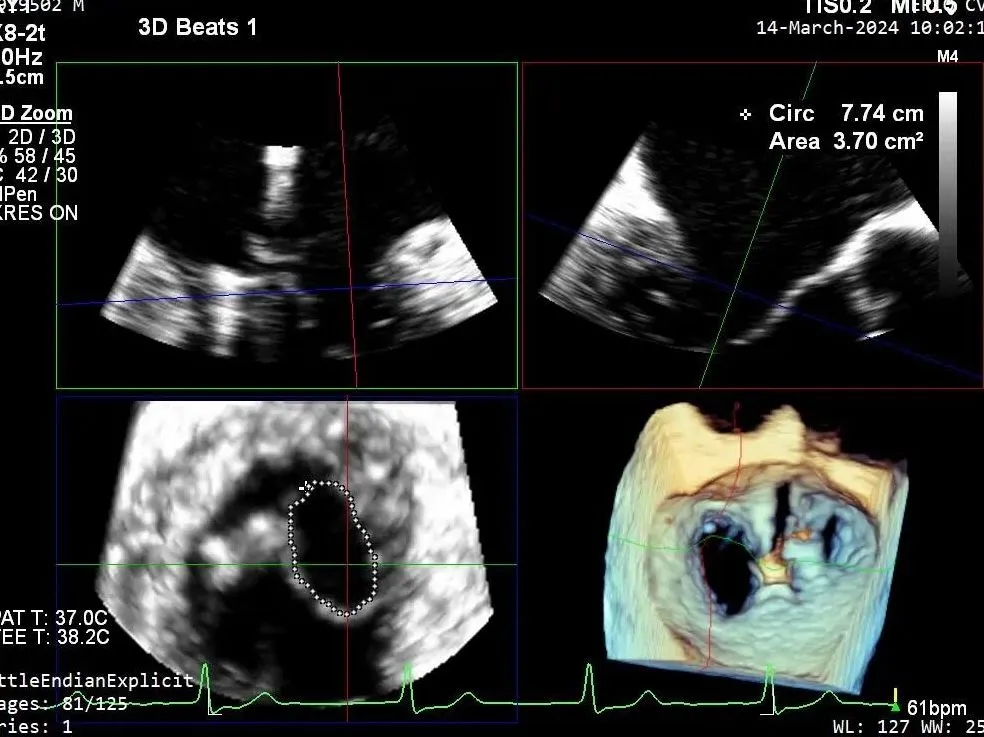

超声心动图:

二尖瓣后叶活动受限,呈房源性栓系,以P3区为重,二尖瓣前叶假性脱垂,二尖瓣瓣环前后径49mm,左右径40mm。

PISA法测r=12mm,EROA=0.72cm2,RVOL=100ml,RF 26%。LVEDD 57mm,左房71*59*77mm,右房55*69mm,LVEF 70%。

超声提示:

二尖瓣反流(重度,4+级,Carpentier I型)

三尖瓣反流(轻度)

主动脉瓣反流(轻度)

双房及心耳内未见确切血栓回声